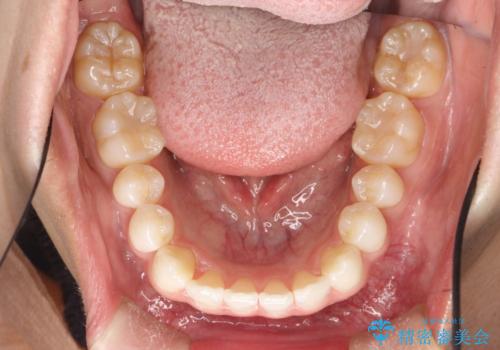

インビザラインによる矯正治療(非抜歯) 下の前歯の歯並びの改善

- 主に下の歯並びの改善を主訴としてご来院されました。

右下の犬歯と前歯が大幅に重なっているのと、歯の向きも大きく横に倒れています。この部位の正常な配列のためには、3次元的に大幅な移動が必要となりました。

マウスピース枚数 初回35枚 + 追加13枚

概ね1年弱で治療が完了しました。

前歯の大きな3次元的移動を可能にするために、当院独自の工夫を随所に盛り込み、狙い通りの治療結果を得られました。